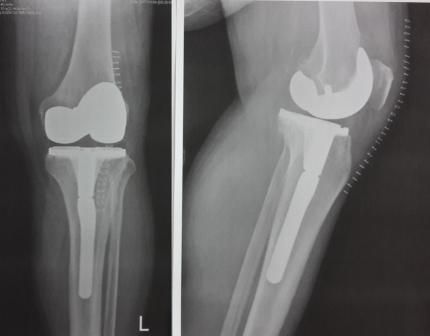

Dr hab. n. med. Ireneusz Babiak - ponad 30-letnie doświadczenie zawodowe zdobywane w trakcie pracy i szkoleń w szpitalach klinicznych w Polsce, Niemczech, Szwajcarii i Szwecji. Specjalizuje się w diagnostyce i leczeniu chorób stawów kolanowych, biodrowych, barkowych, kręgosłupa, deformacji stopy, terapii podciśnieniowej ran (tj NPWT) systemami VAC, Pico, Avelle. Wykonuje operacje: endoprotezy stawu biodrowego i kolanowego ( w ostatnim roku 200 endoprotez implantowanych osobiście i asysta do kolejnych 200 endoprotez), zespół cieśni nadgarstka, palec zatrzaskujący, paluchy koślawe (haluxy), palce młotkowate, zespolenia złamań kości, zaburzenia zrostu, operacje rewizyjne endoprotez stawów, operacyjne leczenie zapaleń kości stawów z zastosowaniem biomateriałów, przeszczepy skóry. Do roku 2017 adiunkt oraz ordynator Oddziału IV w Klinice Ortopedii Traumatologii Warszawskiego Uniwersytetu Medycznego (WUM), oraz wykładowca na English Division Medical University of Warsaw. W roku 2018 stanowisko överläkare - specjalista odpowiedzialny za endoprotezoplastykę biodra i kolana w Klinice Ortopedii w Eskilstunie w Szwecji. Wykładowca na kursach szkoleniowych z operacji rewizyjnych endoprotez stawów, zapaleń kości i stawów, planowania w endoprotezoplastyce stawów, powikłań w ortopedii. Członek towarzystw naukowych: PTOiTr (Polskie Towarzystwo Ortopedyczne i Traumatologiczne), EBJIS (European Bone and Joint Infection Society), PTZS (Polskie Towarzystwo Zakażeń Szpitalnych).

Zdjęcia i filmy